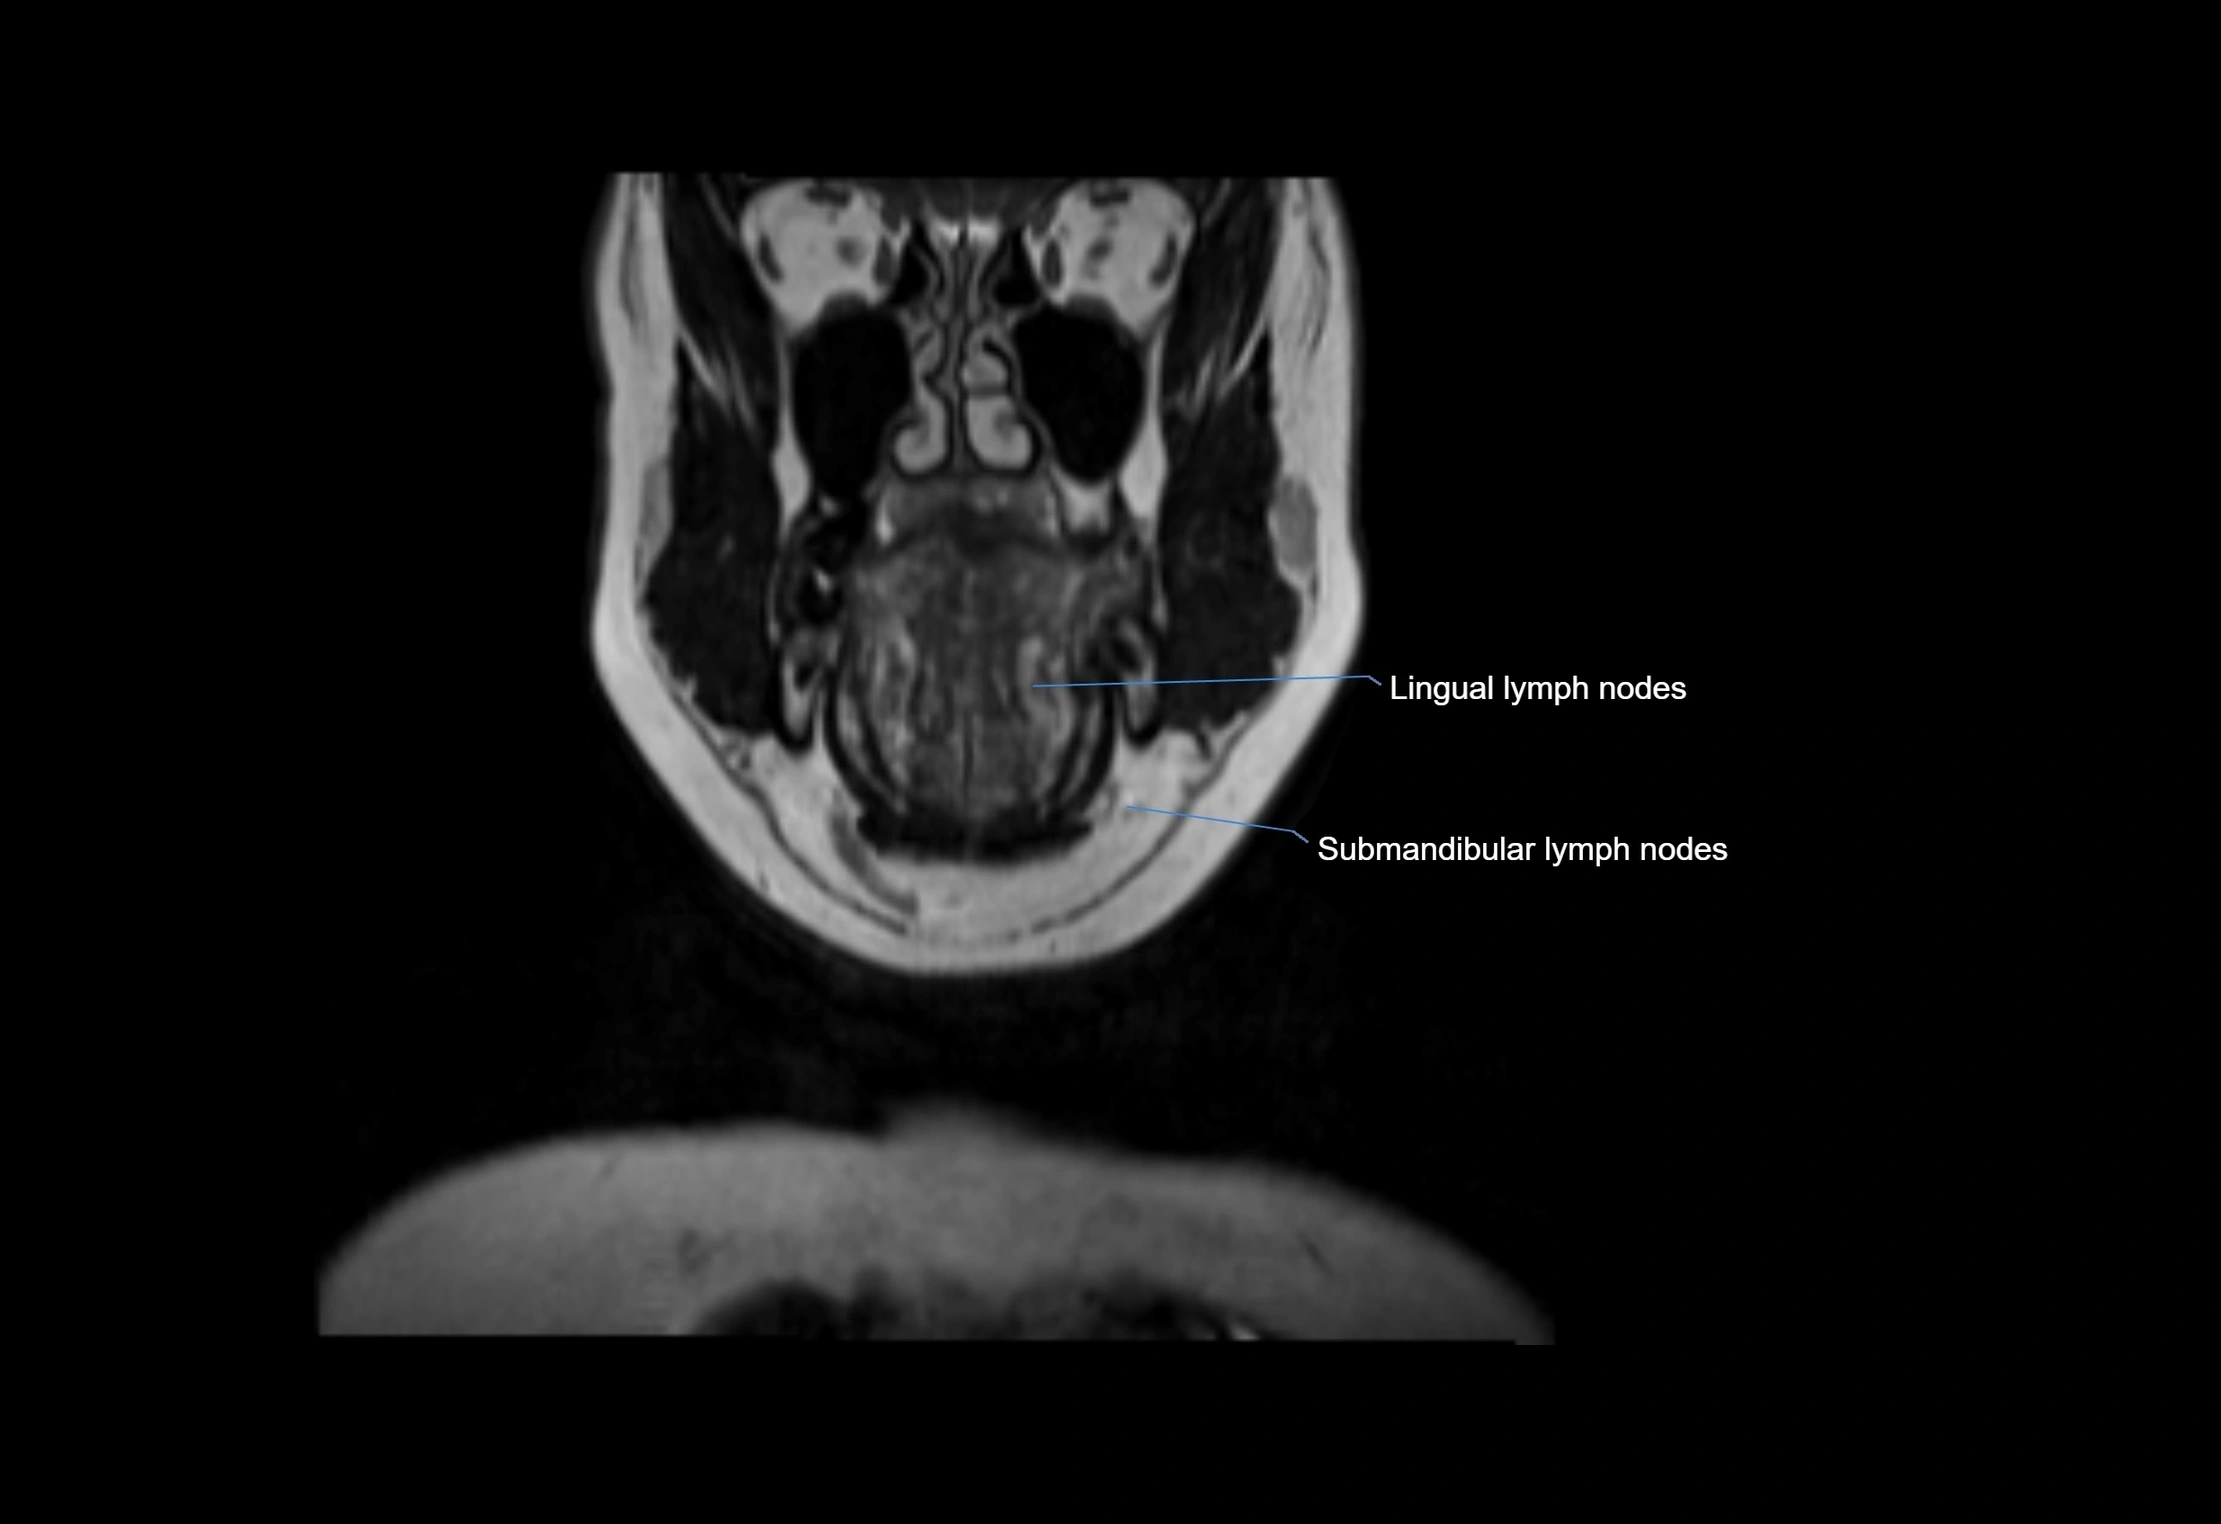

MRI Appearance

T1-weighted images:

• Normal accessory nodes appear as small, oval hypointense to intermediate signal structures within subcutaneous fat

• Surrounded by hyperintense fat, enhancing contrast for visualization

• Pathological nodes may appear enlarged or rounded, sometimes with cortical thickening

T2-weighted images:

• Nodes show intermediate signal, with surrounding fat bright

• Useful for detecting edema, inflammation, or infiltration

• Fatty hilum may appear slightly hyperintense relative to cortex

STIR (Short Tau Inversion Recovery):

• Fat suppression enhances visualization of edematous or pathological nodes

• Normal nodes appear low to intermediate signal, while inflamed or metastatic nodes appear hyperintense

• Useful for detecting subtle lymphadenopathy or early pathology

MRI images